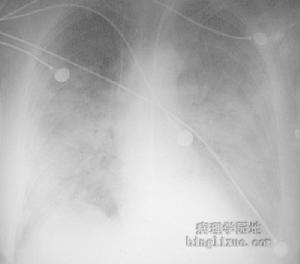

線顯示的不規則病灶發病機制:孢子絲菌病主要侵犯皮膚、黏膜、局部淋巴系統,引起肉芽腫性損害。肺內病變初期為段性分布的支氣管炎和支氣管肺炎。病理變化為非特異性炎症改變,浸潤的炎症細胞包括中性粒細胞、淋巴細胞、漿細胞及少量類上皮細胞。隨病程遷延,形成慢性非特異性肉芽腫,導致結節性肺炎,典型病變由內向外依次為:中央區為慢性化膿區,主要由中性多核白細胞所組成的小膿瘍,並混有少數組織細胞和淋巴細胞;周圍有大量上皮細胞和多核巨細胞;外圍主要為淋巴細胞和成纖維細胞。活檢組織切片先以澱粉酶在37℃處理1h後作PAS染色,可見4~6μm大小的圓形或卵圓形小體,有時尚可見4~8μm長的雪茄菸形小體及星狀小體。